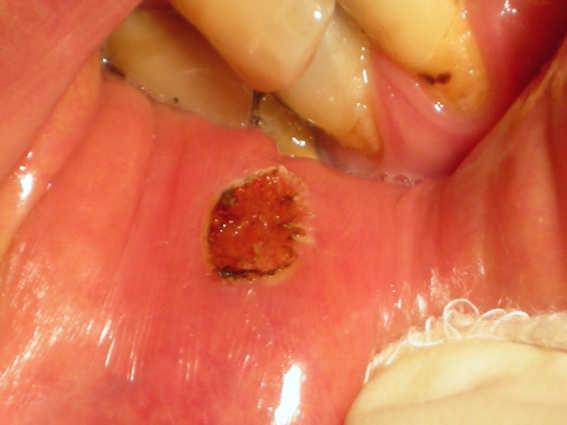

Morsicatio buccarum

Morsicatio buccarum (also known as "Chronic cheek biting," and "Chronic cheek chewing") is a cutaneous condition characterized by chronic irritation or injury to the buccal mucosa from repetitive chewing, biting or nibbling produces characteristic changes in the tissue.